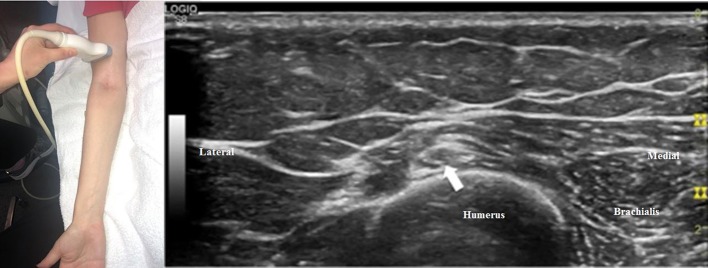

The radial nerve bifurcates into the superficial radial sensory nerve and the deep motor nerve at the antecubital fossa. When the transducer is placed at the antecubital fossa to obtain a cross-sectional view (Figure 1), both the sensory and motor branches of the radial nerve are visualized between the brachialis and brachioradialis muscles. At this site (or within 1 cm proximally and distally), the ultrasonographer can assess for fibrous bands anterior to the radiocapitellar joint, the recurrent radial vessels of the leash of Henry, and the proximal edge of the ECRB. Moving the transducer proximally (Figure 2), the radial nerve can be identified adjacent to the humerus, coursing through the spiral groove between the long head of the triceps and the humerus. Near the spiral groove, the deep brachial artery can be identified adjacent to the radial nerve. If necessary, the radial nerve can be traced all the way proximally to the terminal branch of brachial plexus.

Figure 2.

The transducer has been moved proximally compared to Figure 1, and the radial nerve (arrow) can now be seen adjacent to the humerus (the convex, hyperechoic structure just deep to the nerve) in the spiral groove.